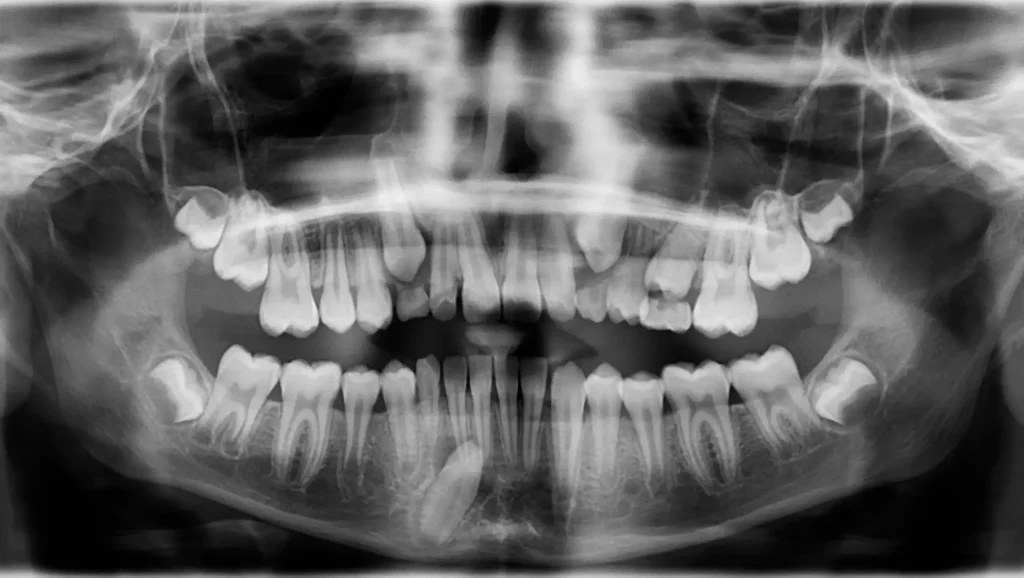

El diagnóstico principal para este caso fue un canino inferior impactado.

Canino impactado:

Alineación dental:

Estructura ósea:

Relación oclusal: